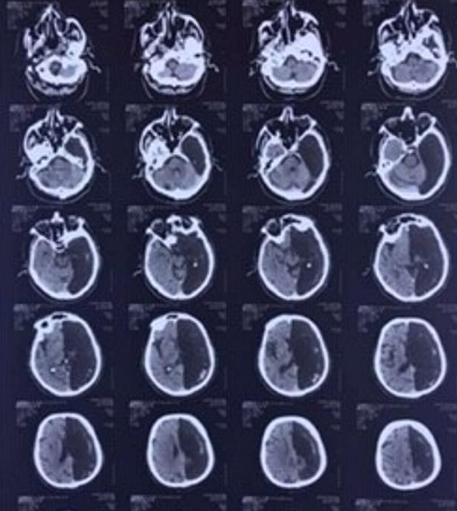

Medics in Moscow made the stunning discovery whilst running a CT scan when the man was hospitalized after a mini-stroke.

The Russian ex-soldier had no clue that there was a black hole in his skull where the left hemisphere of the brain is supposed to be.

It is not yet clear what fills the hole in the skull of the man. In a similar condition that is rare, known as hydranencephaly, a child is born with a majority of the brain’s tissue missing and fluid takes its place.